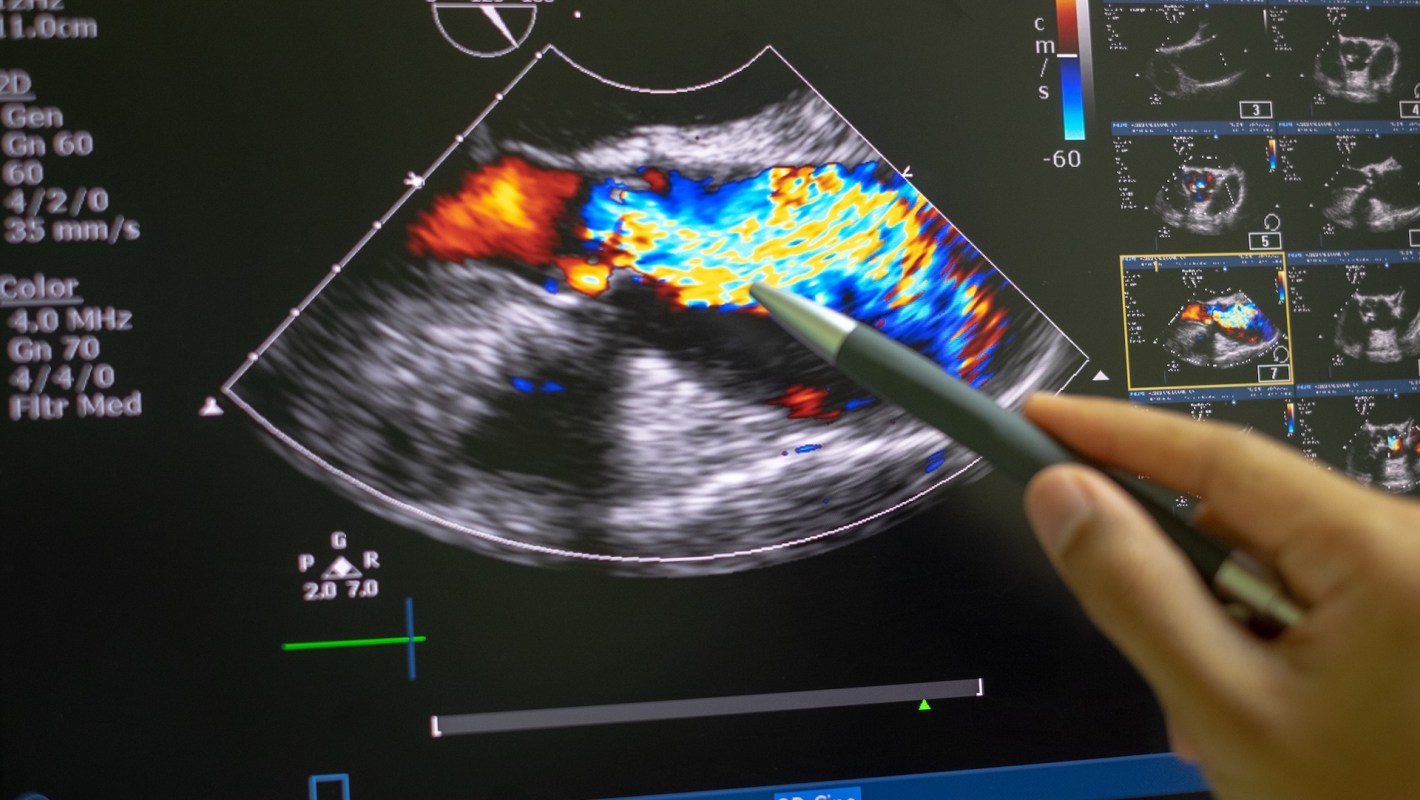

The research team gathered 11 estimates of the risk of myocardial infarction (heart attack) and 15 for stroke.

The study's results stated that e-cigarette users are generally 1.53 times more likely to have a heart attack than non-e-cigarette users. But if an e-cigarette user previously smoked conventional cigarettes, their risk went up to about 2.52 times more likely.

Stroke analysis was similar. E-cigarette users are generally 1.05 times more likely to have a stroke. If a user smoked conventional cigarettes in the past, that risk jumped to 1.73 times more likely.